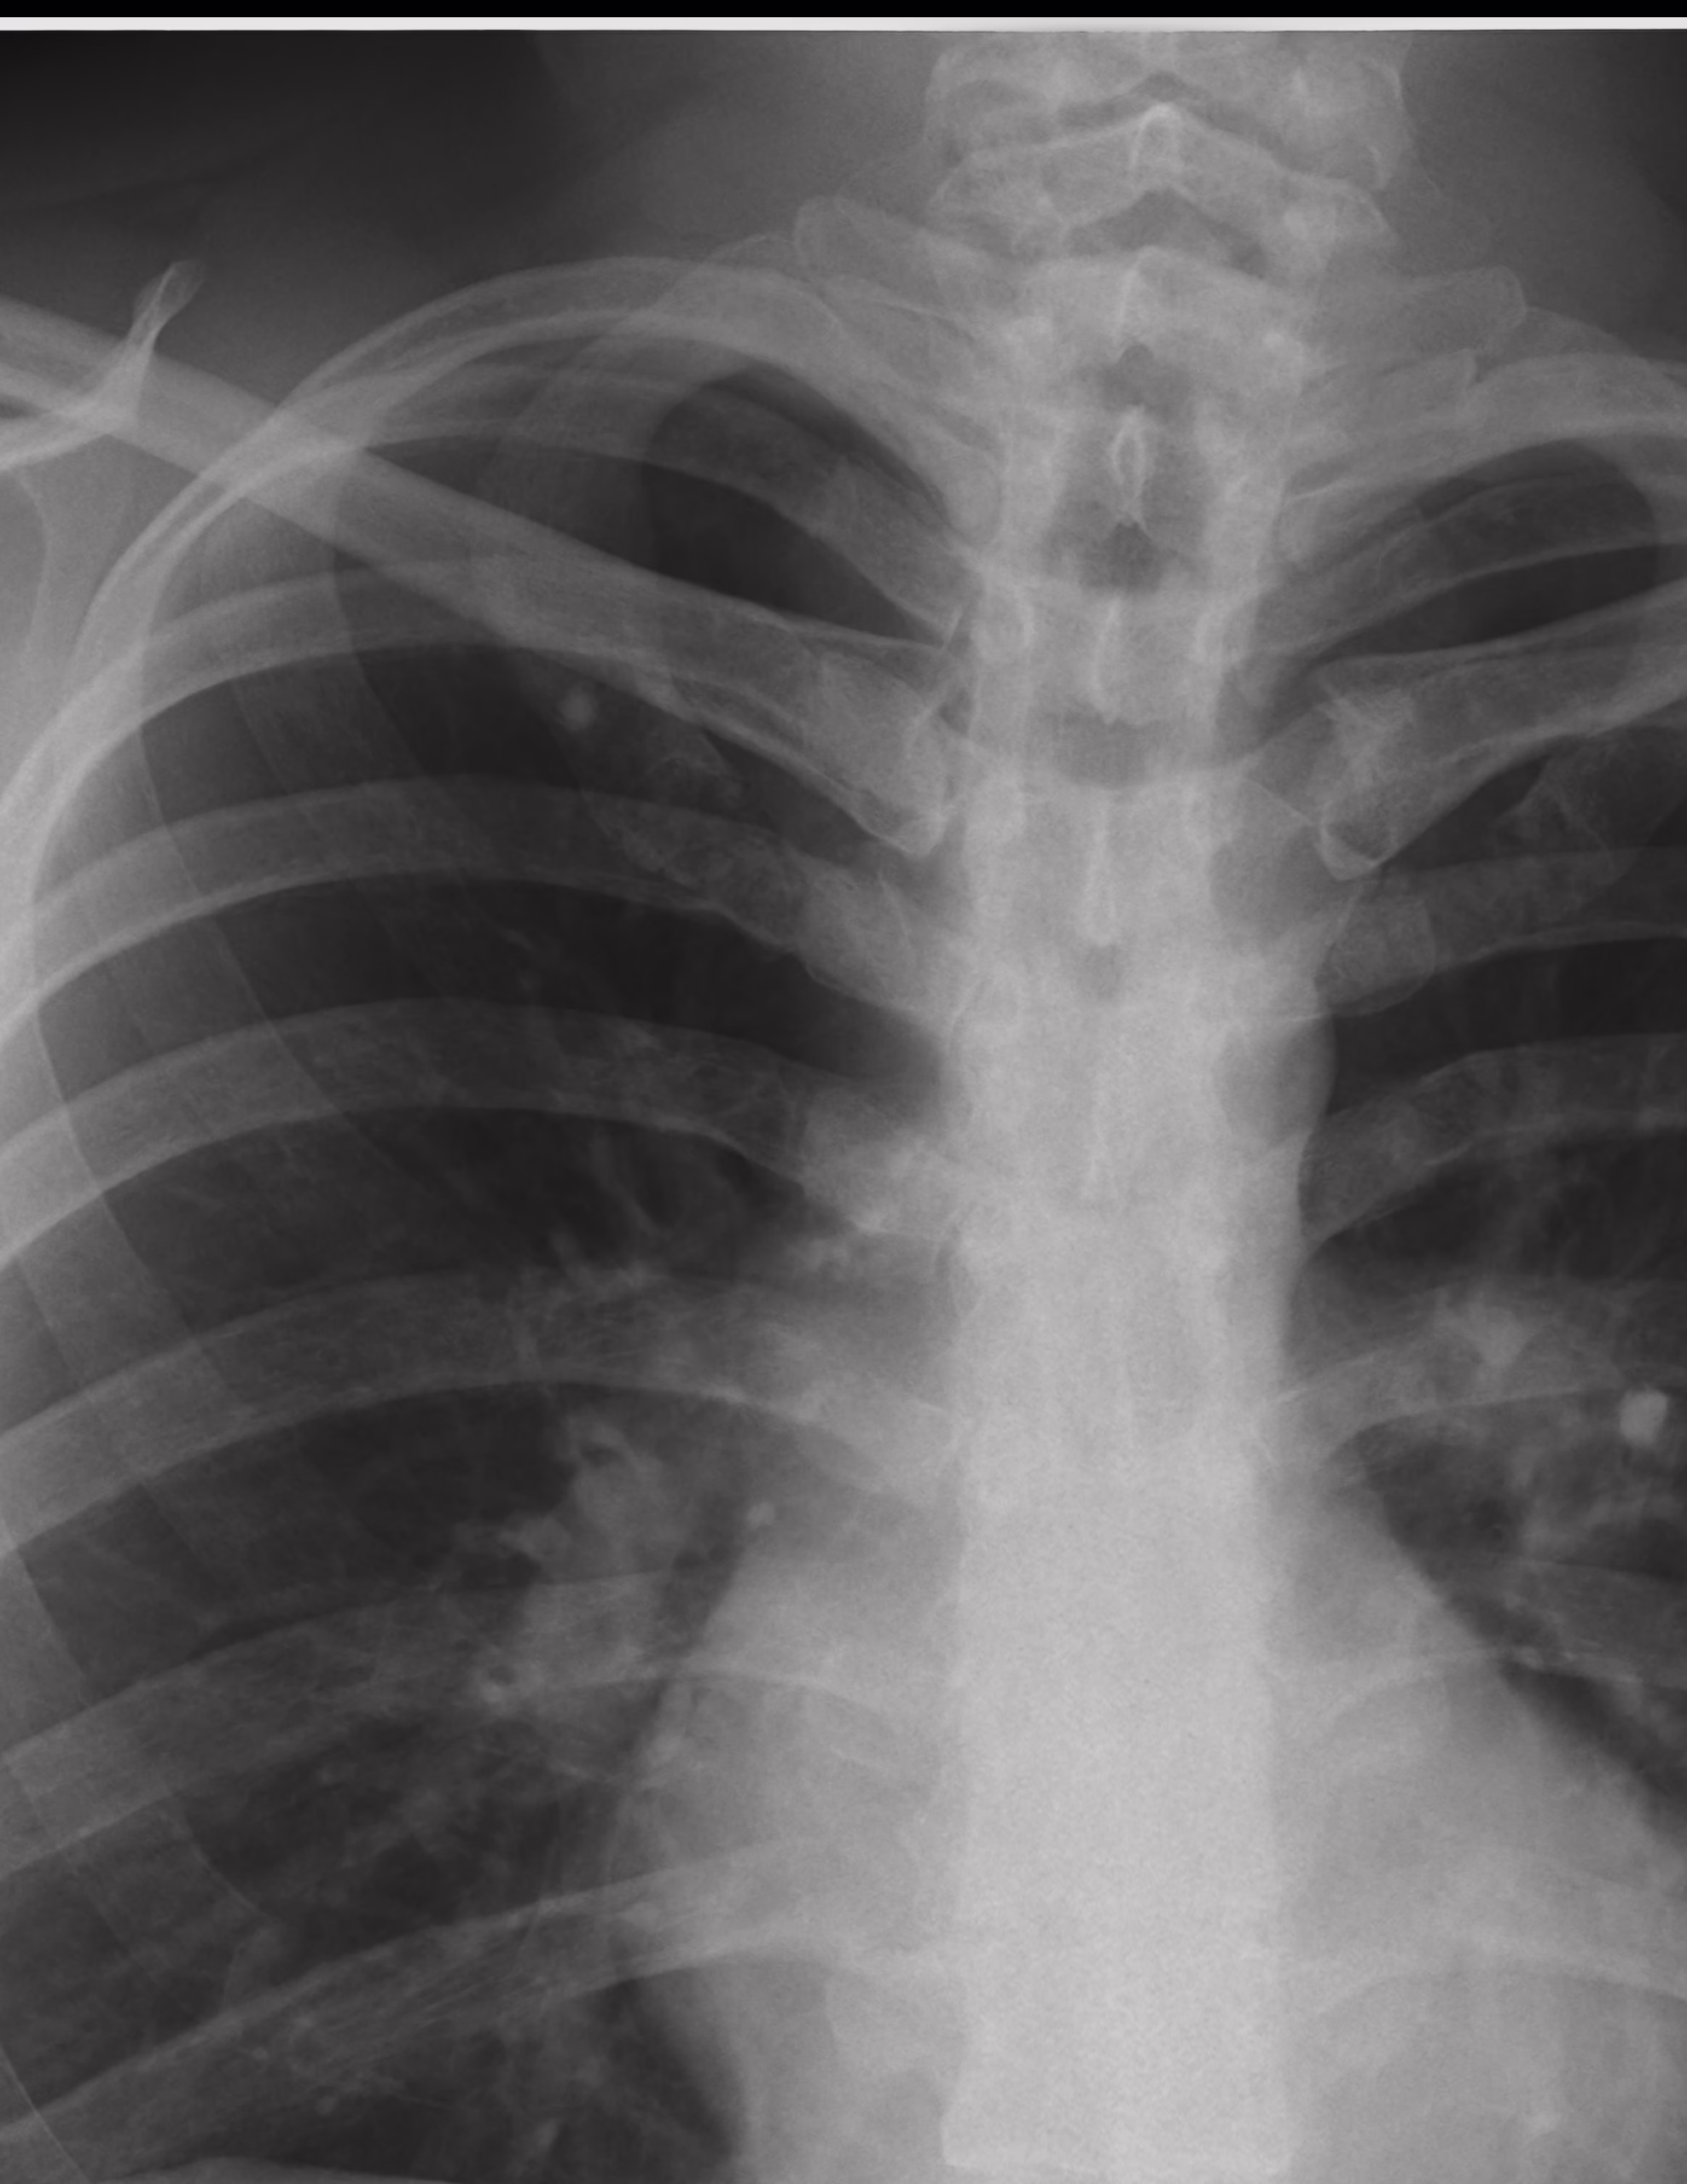

Imagen radiopaca proyectada en el primer arco costal derecho de 4.5 mm. que sugiere granuloma pulmonar calcificado.